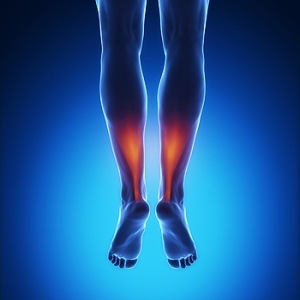

The purpose of the body’s circulation system is to transport blood, oxygen, and nutrients throughout the body. A reduction of blood to a specific part of the body may cause one to experience symptoms of poor circulation. The most common causes of poor circulation in the feet are obesity, diabetes, and heart conditions such as peripheral artery disease (PAD). Common symptoms of poor circulation include tingling, numbness, throbbing, pain and muscle cramps.

Peripheral artery disease is a common cause of poor circulation in the legs. Symptoms of PAD are cramping, pain or tiredness in the leg or hip muscles while walking or climbing stairs. This pain tends to go away with rest and starts back up when you begin to walk. It is a condition that causes the blood vessels and arteries to become narrow. Although PAD is more common in adults over the age of 50, it may also occur in younger people. A similar condition called atherosclerosis causes arteries to stiffen up due to a buildup of plaque in the arteries and blood vessels.

Blood clots are also a common cause of poor circulation in the feet. Clots may obstruct blood vessels and if they occur in the legs, they may eventually lead to pain and discoloration. This occurrence is commonly known as deep vein thrombosis (DVT) and it may travel to the lungs. Varicose veins are another condition that may lead to poor circulation, and it is caused by incompetence of the valves in the veins. Women who are overweight are prone to developing this condition. Lastly, diabetes, which is correlated with poor blood sugar metabolism may lead to chronic poor circulation. Those with diabetes often suffer from cramping in the legs, calves, thighs and buttocks.

If you are looking for ways to avoid poor circulation there are some tips you can follow. One tip is to avoid sitting for too long. If you plan to sit down for a long period of time, you should try standing up occasionally, to improve your circulation. Another great way to avoid poor circulation is to exercise. Exercise is an excellent way to pump the heart and increase blood flow. Those who suffer from poor circulation should also avoid smoking, reduce their salt intake, and try to lose weight.

If you are experiencing symptoms from poor circulation in your feet, you should consult with your podiatrist to determine the best method for treatment for you. He or she may prescribe medication in addition to recommending specific lifestyle changes to improve your circulation.